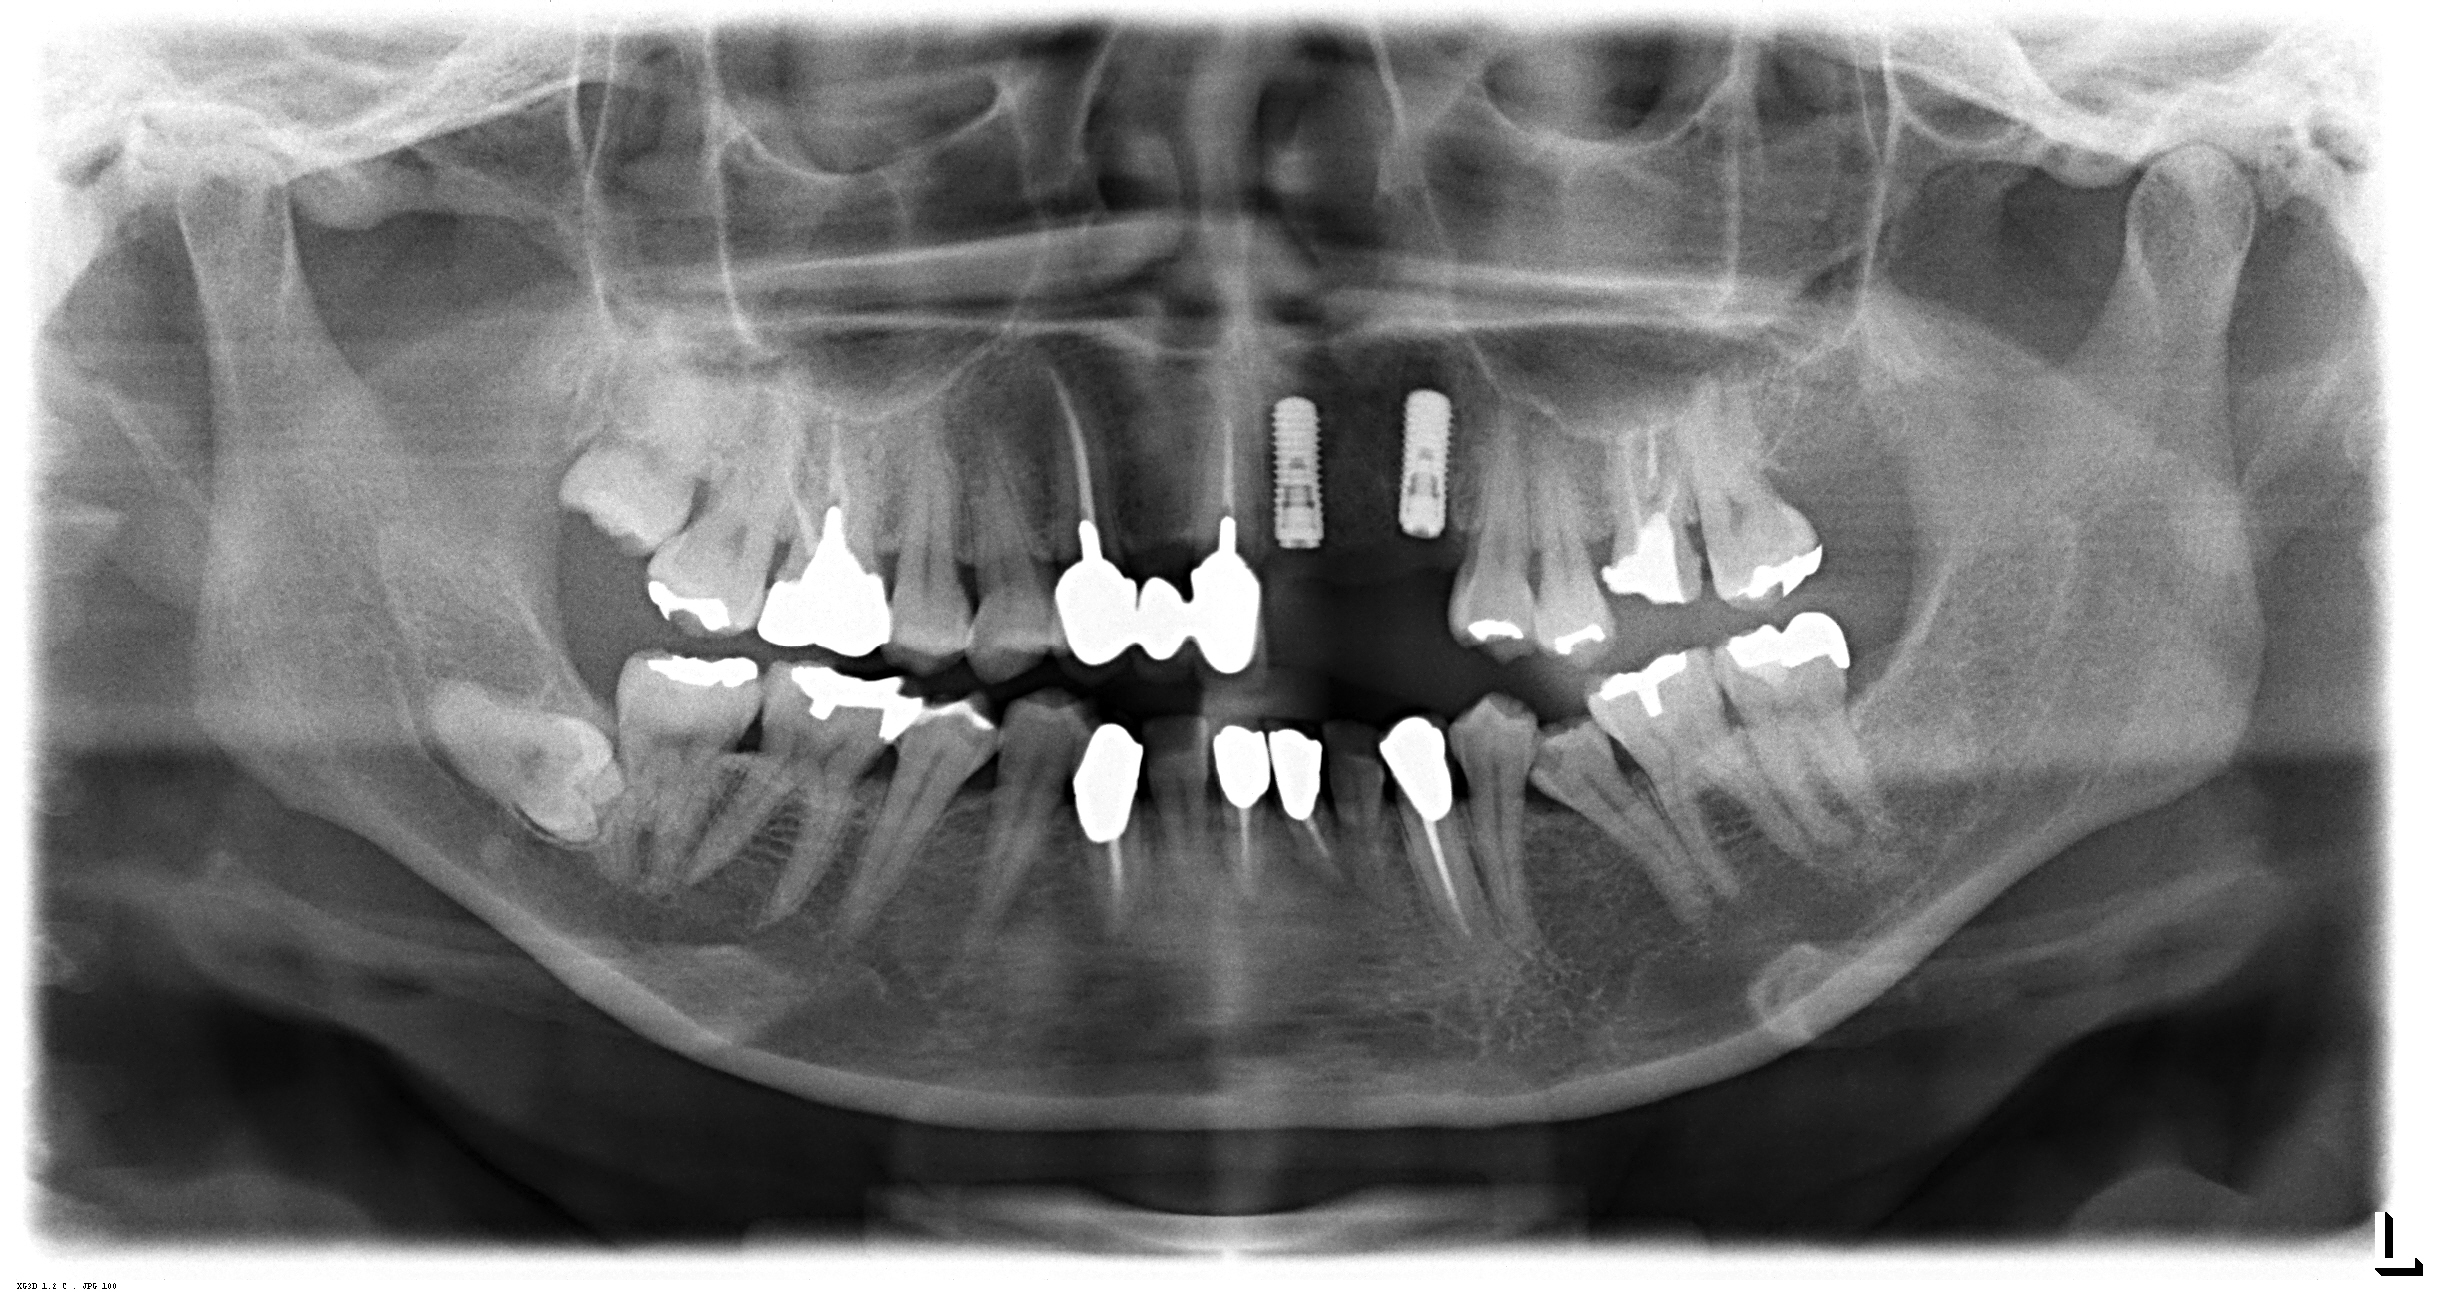

抜歯から8週間後です。左上の前歯から犬歯まで3本が欠損しています。

オペ後のレントゲンです。